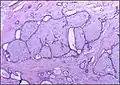

Fibroadenoma histology (H&E). The image demonstrates intracanalicular morphology (bottom left) and pericanalicular morphology (top right) -

Fibroadenoma of the breast is a benign tumor composed of a biplastic proliferation of both stromal and epithelial components.[12][13] This biplasia can be arranged in two growth patterns: pericanalicular (stromal proliferation around epithelial structures) and intracanalicular (stromal proliferation compressing the epithelial structures into slit-like spaces).

These tumors characteristically display hypovascular stroma compared to malignant neoplasms.[2][14][9] Furthermore, the epithelial proliferation appears in a single terminal ductal unit and describes duct-like spaces surrounded by a fibroblastic stroma. The basement membrane is intact.[15]